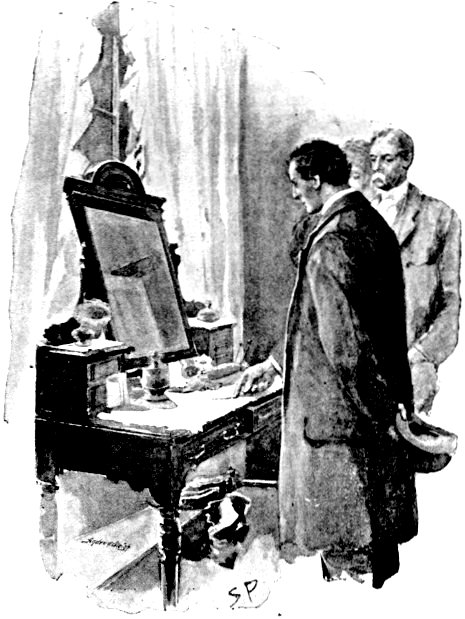

"I FELT HER PULSE."